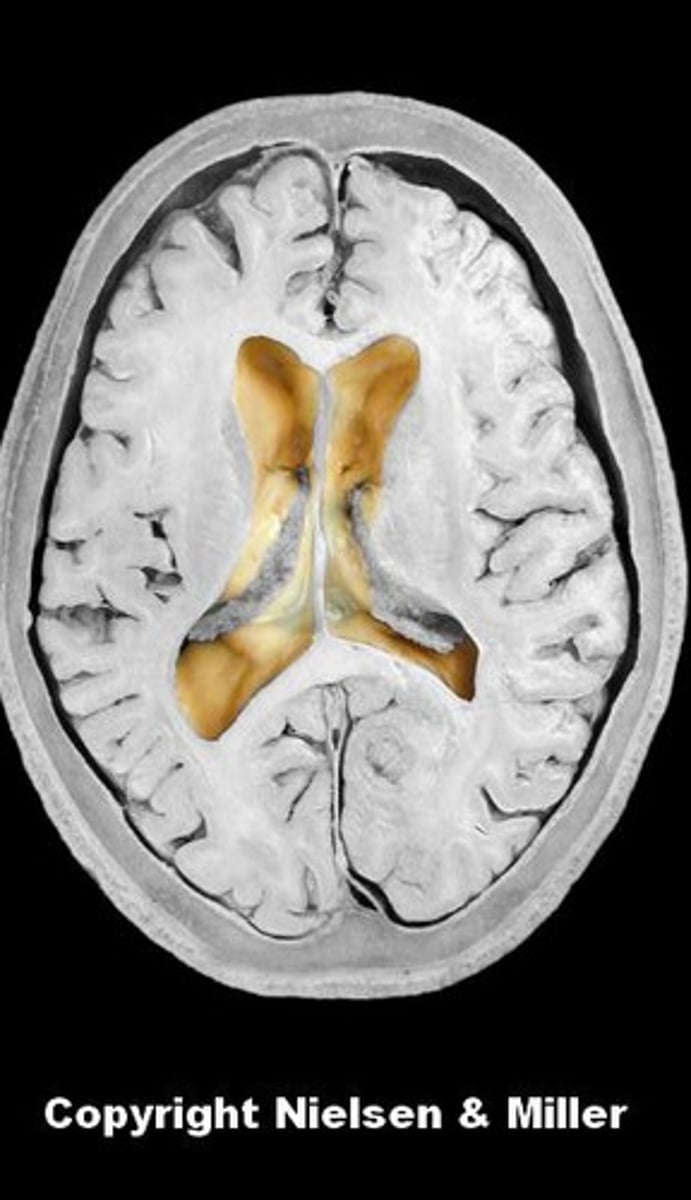

lateral ventricles